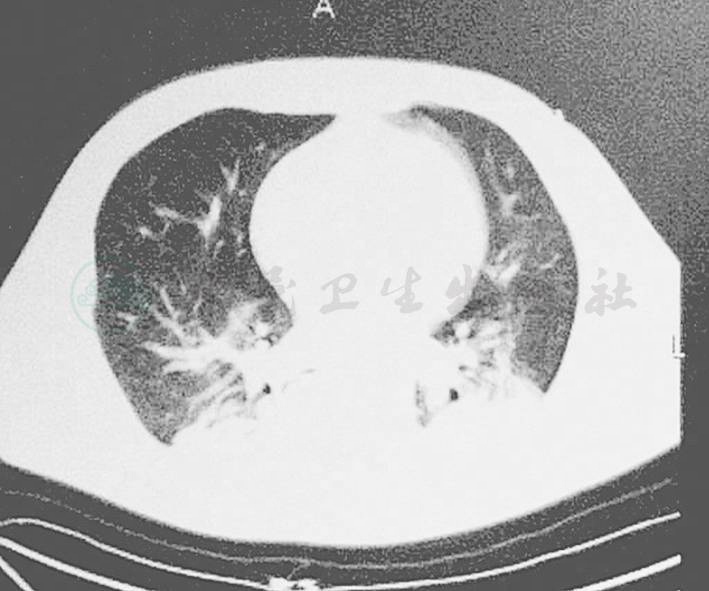

3月4日患者再次出现发热,体温波动于38~38.8℃,血常规示WBC 3.63×109/L,N 79.14%,Hb 80g/L,PLT 14.4×109/L,痰培养提示鲍曼不动杆菌,G试验连续增高2次,肺CT(图1,图2)示双肺野内可见多发片状高密度影,右侧胸腔积液;上腹CT示胰头区脂肪间隙欠清晰,胆囊密度稍高,欠均匀,考虑患者出现重症肺炎,且为细菌合并真菌感染,由于患者存在糖尿病,感染难以控制,故停用米卡芬净及美罗培南,将抗生素调整为头孢哌酮-舒巴坦钠3.0g,每8小时1次,利奈唑胺注射液600mg,每12小时1次,及伏立康唑注射液200mg,每12小时1次治疗,并行气管切开,继续严格控制血糖及行CRRT等治疗。

图1 双肺野内可见多发片状高密度影

图2 双肺野内可见多发片状高密度影,其内可见空气支气管征